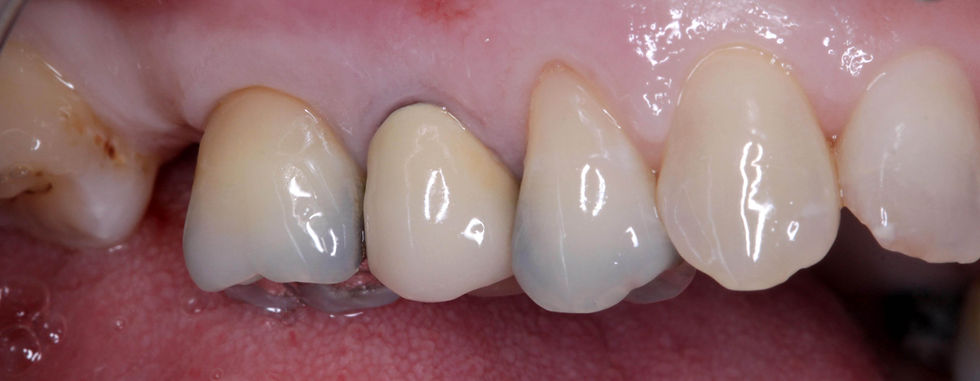

Initial clinical images of the crown on the 1.5.